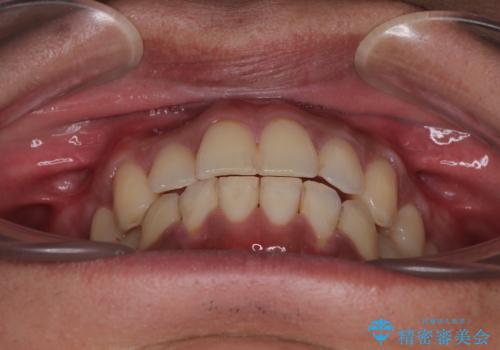

- 今回ご紹介するのは、

「過去に他院で矯正治療をしたものの、前歯の後戻りが気になってきた」

という理由でご来院された患者様です。

診察したところ、上下顎前歯部に軽度の叢生(ガタつき)が認められます。

目立たない装置を希望されたのでインビザライン ライトパッケージで治療を行うことになりました。